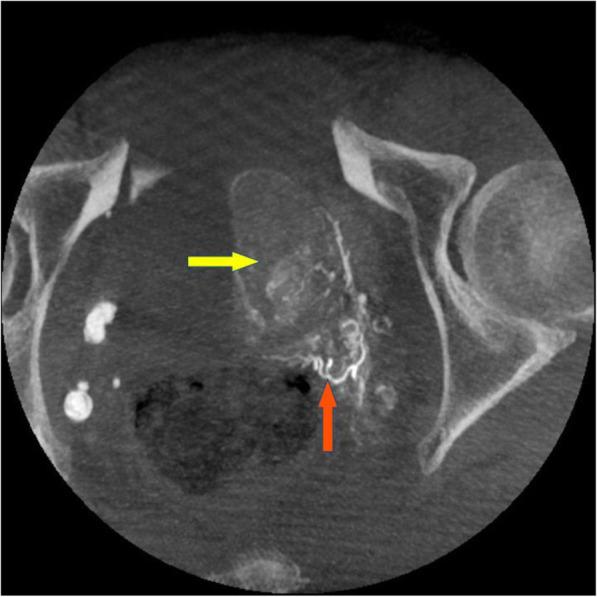

前列腺动脉栓塞术的先进图像引导——一份多中心技术说明。

Advanced image guidance for prostatic artery embolization - a multicenter technical note.

Prostatic artery embolization (PAE) is associated with patients' quality of life improvements and limited side effects compared to surgery. However, this procedure remains technically challenging due to complex vasculature, anatomical variations and small arteries, inducing long procedure times and high radiation exposure levels both to patients and medical staff. Moreover, the risk of non-target embolization can lead to relevant complications. In this context, advanced imaging can constitute a solid ally to address these challenges and deliver good clinical outcomes at acceptable radiation levels.

This technical note aims to share the consolidated experience of four institutions detailing their optimized workflow using advanced image guidance, discussing variants, and sharing their best practices to reach a consensus standardized imaging workflow for PAE procedure, as well as pre and post-operative imaging.

This technical note puts forth a consensus optimized imaging workflow and best practices, with the hope of helping drive adoption of the procedure, deliver good clinical outcomes, and minimize radiation dose levels and contrast media injections while making PAE procedures shorter and safer.